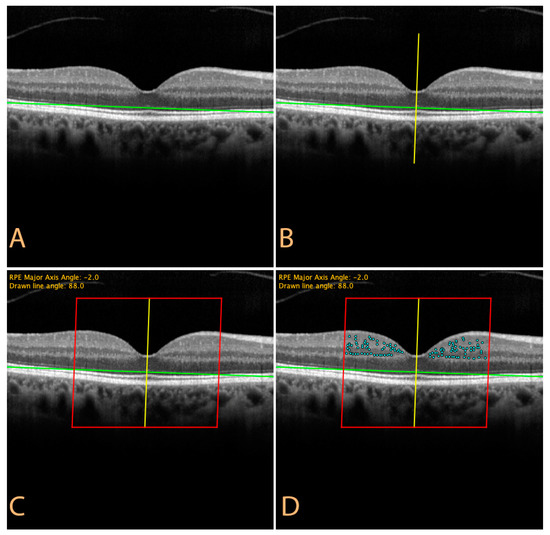

2.3. HRS Counting